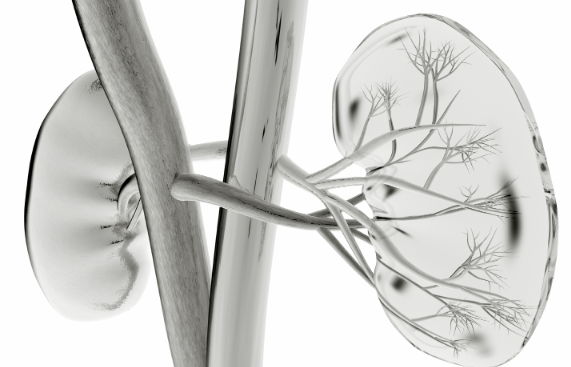

Renal Artery Stenosis

04/28/2011

Donald G. Vidt, MD

<p>In imaging studies in patients older than 55 years with suspected coronary artery disease or peripheral vascular disease, more than 80% of renal artery lesions are associated with generalized...